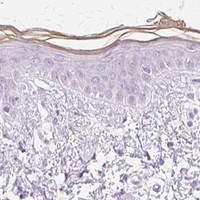

Enhanced - Independent antibodies

Protein distribution across 45 tissues similar between the independent antibodies HPA040171 and HPA070372.

Cerebral cortex

Esophagus

Lymph node

Skin 1